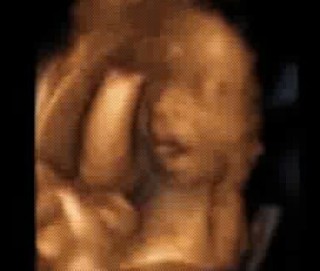

里帰りで初めての4Dエコーでした♪ 5ヶ月の時に男の子と言われ、おまたを隠していて見せてくれなかったのですが、しっかり見せてくれて、まさかの女の子でした!!嬉しいです♪ 1380グラムとのことです!!

今まで、ずっと下を向いていたので4Dエコーが撮れなかったんですが、やっと、回転してくれて、上向いてくれました!